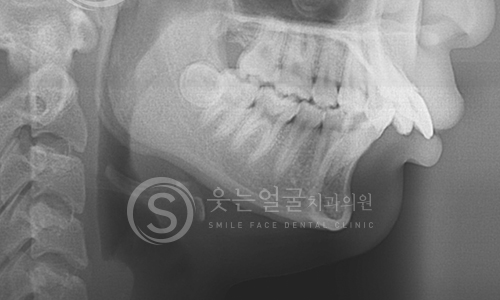

한눈에 보는

임플란트 전후사진